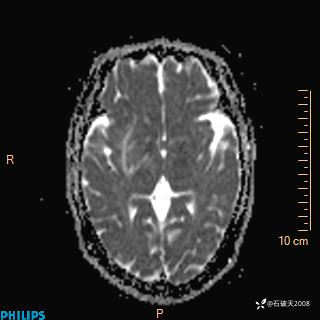

2020.11.14MR

T2

T1

FLAIR